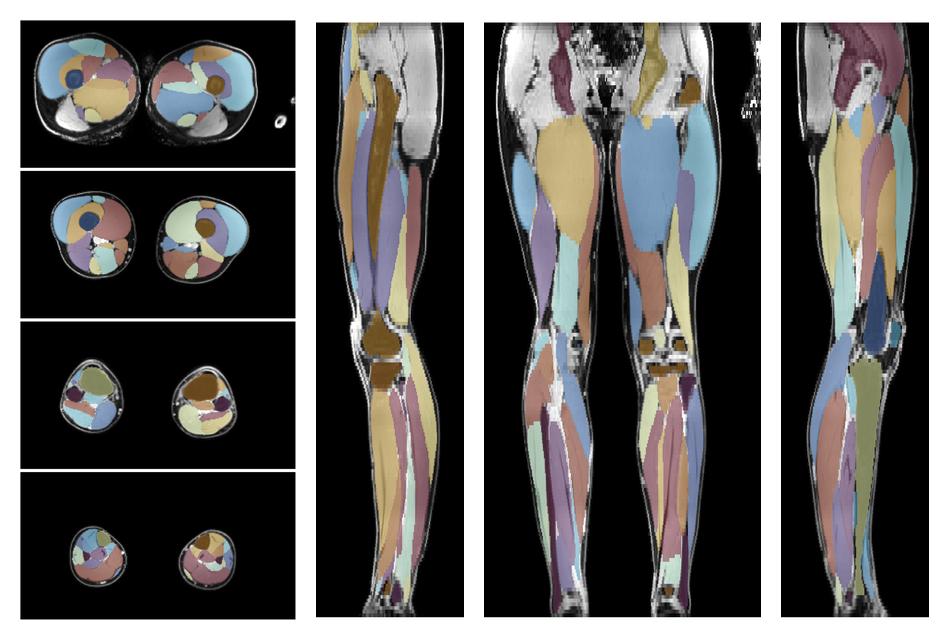

• Automated muscle and bone segmentation.

Overlay of automated muscle segmentation labels on dixon water image.